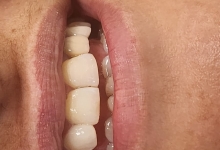

SUPRAPROTEZAREA PE IMPLANT